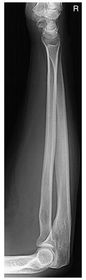

What are the routine exams of the forearm? AP Lateral

AP Forearm 60-75 kV 40 SID 14x17 IR nongrid CR @ mid forearm MUST SEE entire radius/ulna humeral epicondyles slight superimposition of distal radioulnar joint

Lateral Forearm 60-75 kV 40 SID 14x17 IR nongrid CR @ mid forearm MUST SEE 90 degree elbow flex entire radius/ulna head of ulna superimposed over radius